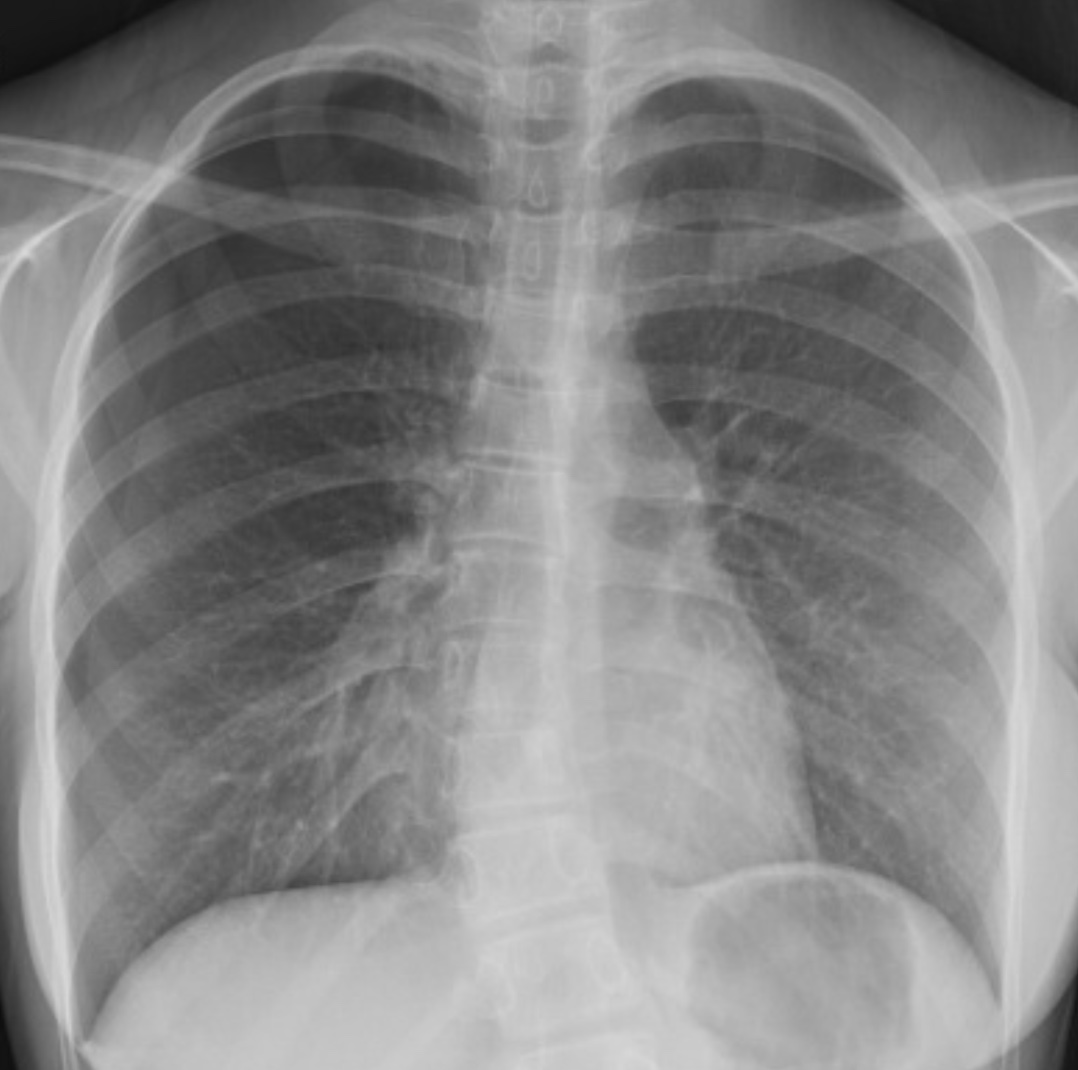

X-ray is shown. What's the diagnosis? Scroll down for answer.

Diagnosis : Spontaneous Pneumothorax (right sided, in this case)

Chest x-ray - displaced pleural line with absent lung markings extending from visceral pleura (lung edge) to parietal pleura (chest wall)